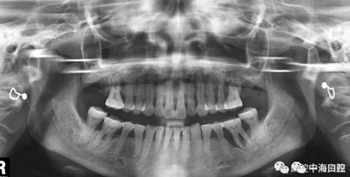

由于智齒的生長位置特殊,導(dǎo)致了拔除難易不同,如智齒出現(xiàn)橫著長或者靠近牙神經(jīng)的話,則難度會較高,一般人只需拍個口腔全景片,但相對于智齒靠近神經(jīng)管的情況,還可能需要拍CT,這都很考驗牙醫(yī)的技術(shù)。

下面這兩張圖,據(jù)說拔牙費時1.5小時,收費14000元。